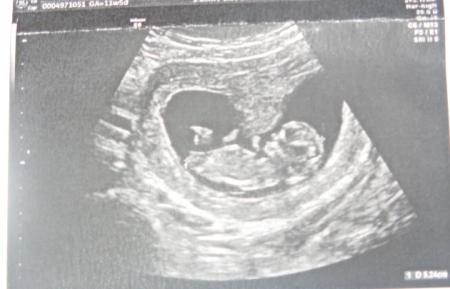

Hallo ihr lieben! Ich komme leider gerade kaum zum lesen und schreiben. Bei meinen 4 großen steht grad auch irgendwie immer was an und zu allem Übel hatten Männe und Hund beide am selben Tag einen kleinen "Unfall". Hund lahmt, bekommt Schmerzmittel und hat Leinenzwang...und Mann hat irgendeine komische Absplitterung im Ellenbogen. Dafür gibts auch was schönes zu berichten. Ich war heute in der Uni Tübingen wegen meiner bevorstehenden OP. Dem kleinen Bärchen geht es prima, stolze 52,4 mm und absolut zeitgerecht entwickelt. OP-Termin ist für den 02.06 angesetzt...einen Tag vorher ist das Narkosegespräch. Ansonsten gehts mir recht gut. Blutungen hatte ich keine mehr und das Hämatom war ja auch nicht mehr zu sehen. Ich hab nur noch wenig mit Übelkeit zu kämpfen, bin dafür aber teilweise recht müde. Ich muss noch weiterhin hochdosiert Utrogest nehmen, vor der OP dann noch scheidendesinfizierende Zäpfchen. Hoffentlich kann ich meine Schwangerschaft nach der OP dann endlich genießen.... hier noch ein Bauchbild (5. Kind/ 12. SSW) und ein Bärchenbild für euch. LG Bea

...und hier das Bärchenbild von heute...

Hallo das ist aber ein schönes Bild von deinem kleinen Bauchzwerg - süß! na da war ja einiges los bei euch zuhause. warum musst du denn operiert werden wenn ich fragen darf habe ich das irgendwie nicht mitbekommen?! hmm.. freue mich riesig für euch das mit dem Krümel alles in ordnung ist! lieben Gruß

da hast du aber ein ganz schönes bild von deinem nachwuchs! bin ich ja fast neidisch... aber freut mich das bei euch alles so super ist!